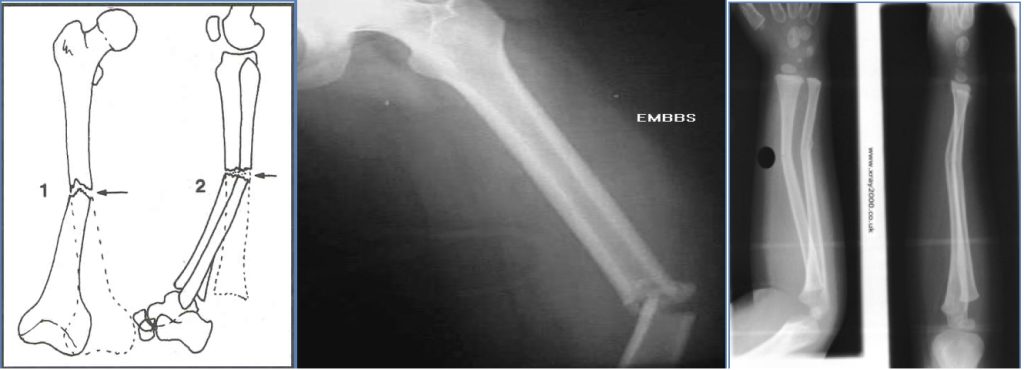

- Displacement?

- Described as % of offset between fragments (e.g. 50%, 100%)

- Angulation?

- Measured in degrees, e.g. “30° lateral angulation of distal femur”

- Rotation?

- Difficult to assess on plain film; inferred from clinical alignment